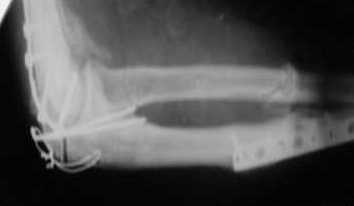

Подскажите пожалуйста, как можно в дальнейшем этому больному помочь. В марте первая операция, пришлось оперировать на 16 сутки в виду инфицированных садин и анемии. Заживление первичным натяжением,раняя разработка после операции, а через 2 нед болевой синдром,и постепенно движения в локтевом суставе ограничились до полного анкилоза. Повторно через 4 месяца вторая операция" артролиз,удаление оссификатов, удаление фиксаторов, реостеосинтез этой же реконструкционной пластиной и винтом" интраоперационно после удаления оссификатов и фиксаторов обнаружил, что перелом не сросшиеся, поэтому пришлось синтезировать заново. Зажило рана первично, объем движений в локтевом суставе сгибание 70, разгибание160, ротационные движения востановились полностью,вроде бы успокоились. Опять постепенно в течении 8 нед после повторной операции постепенно движения ограничились до 80 - 110, на снимке оссификат. Снимки во вложении, буду рад Вашим советам. Спасибо!